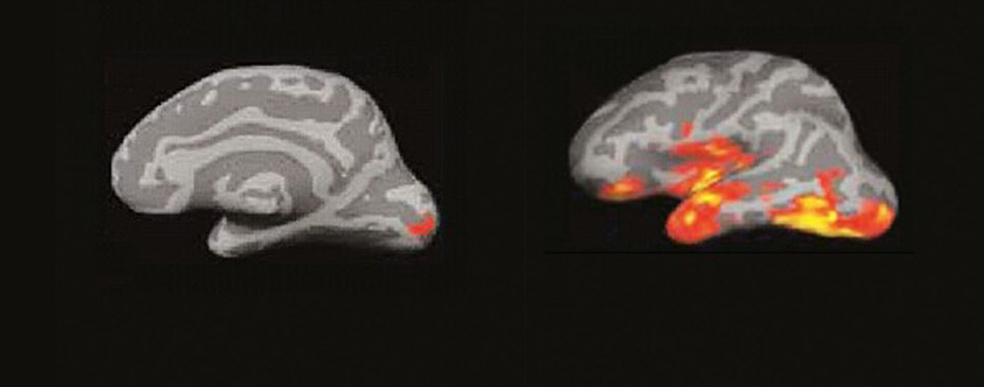

El cerebro del lector: un incendio de ideas

La imagen por resonancia magnética del cerebro de alguien que lee muestra algo parecido a un incendio forestal en un día de viento. Las pavesas vuelan y prenden nuevos conatos en diferentes zonas…

Entre 250 y 460 milisegundos. (A la izquierda) 3. Se produce una explosión de actividad en múltiples áreas de las regiones temporal y frontal del hemisferio izquierdo. El cerebro recopila todo lo que sabe de esa palabra. fonética, función sintáctica, significado… (A la derecha) 4. El ‘incendio’ se extiende, creando circuitos neuronales que conectan los procesos del lenguaje, visuales, espaciales… Comprendemos, sacamos conclusiones y surgen los recuerdos y los pensamientos propios.